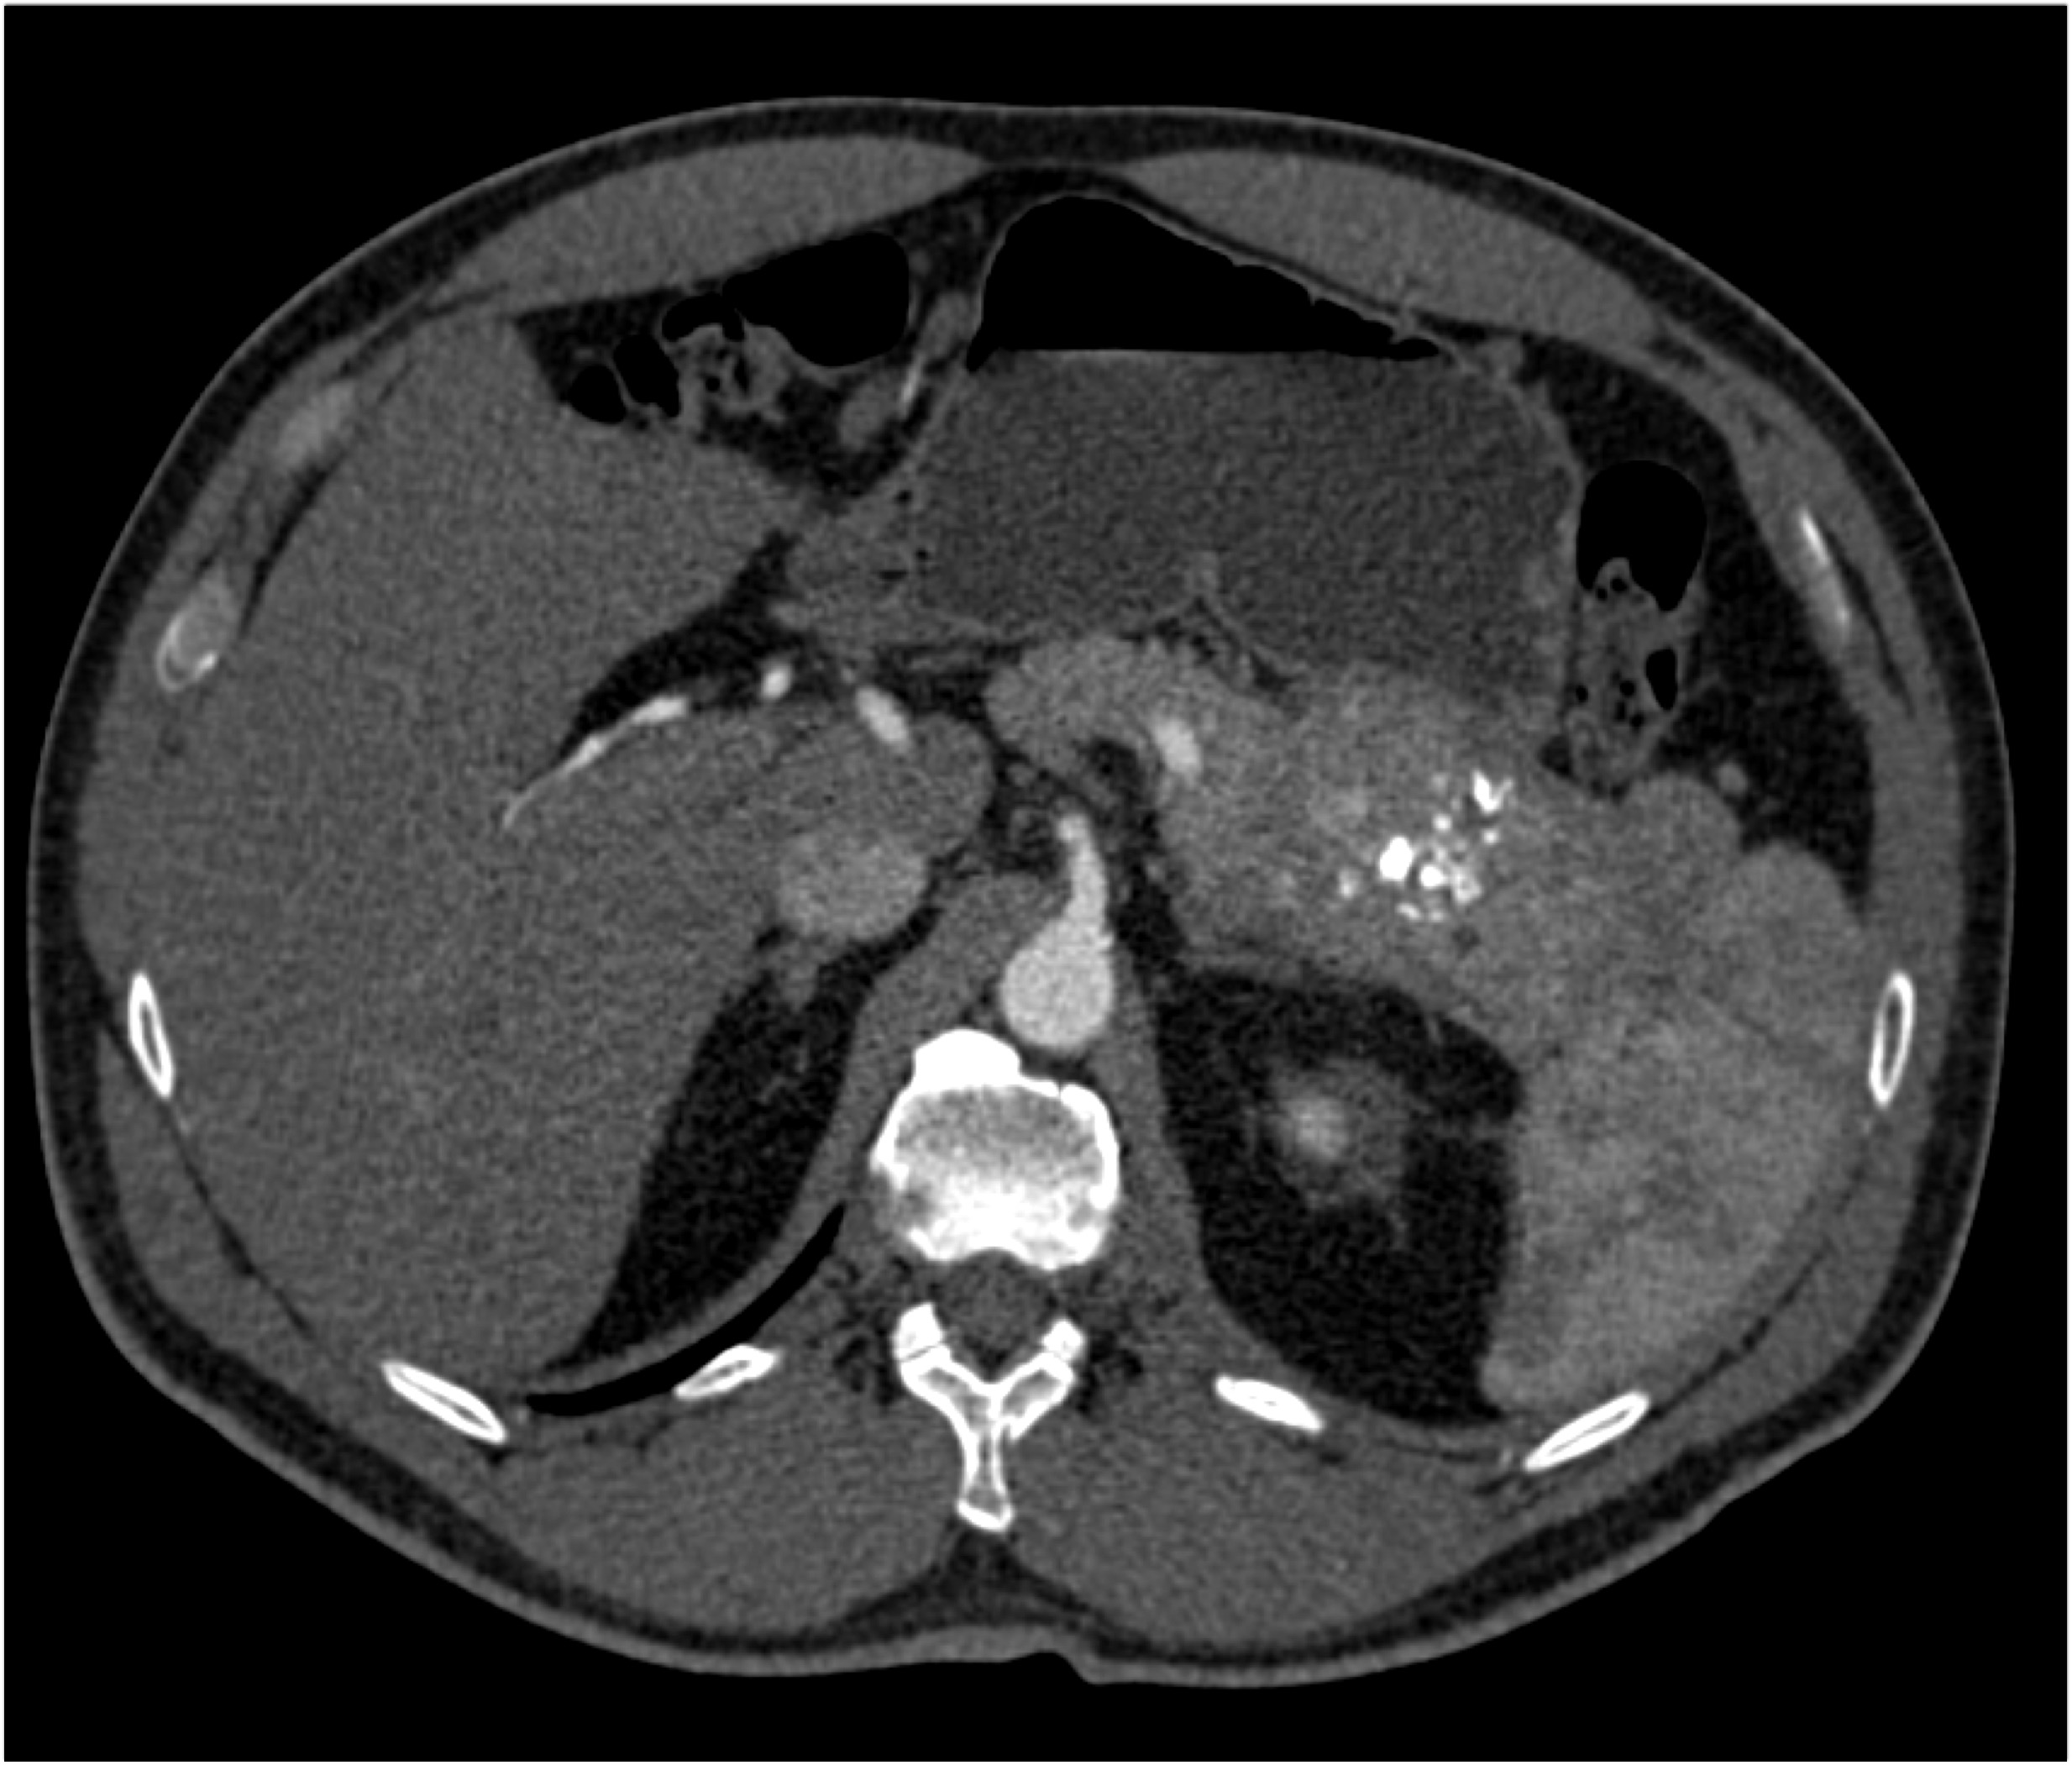

3) The most likely diagnosis in this case is?

hepatoma

cholangiocarcinoma

gallbladder cancer

hepatic adenoma